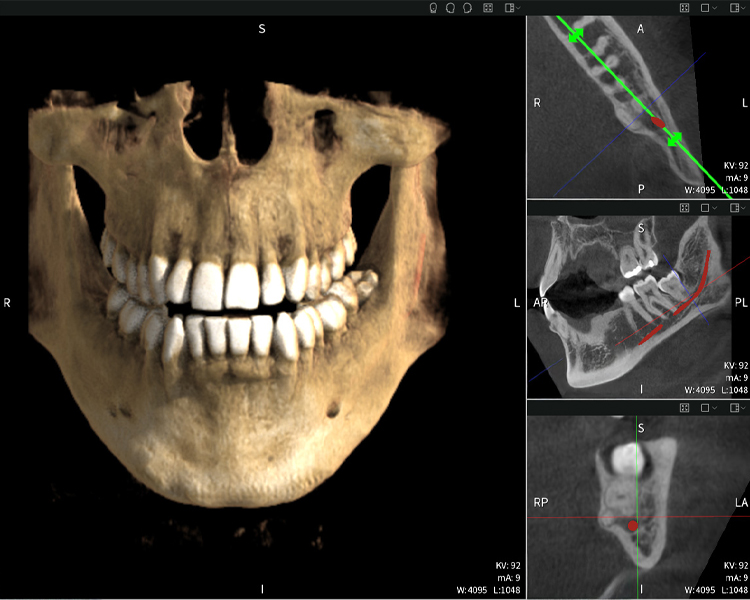

Abbildungen b–d zeigen verschiedene Ansichten einer 3D-Rekonstruktion des Unterkiefers und bieten eine umfassende Übersicht über die Anatomie des Unterkiefers, die Lage der Nerven im Verhältnis zu den Zähnen und ermöglichen die Beurteilung der Zahnsymmetrie und Ausrichtung.

Abbildung d zeigt den bereits vorbehandelten Zahn 48, dessen Krone entfernt wurde und dessen Wurzeln nahe am Nerv belassen wurden, was das hohe Risiko einer Nervenschädigung verdeutlicht.